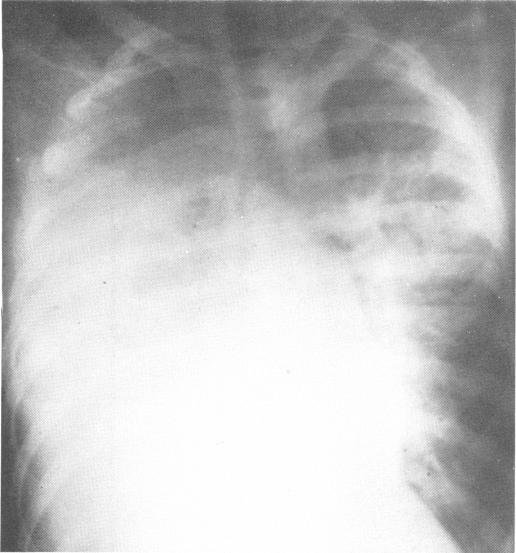

Chylothorax: indications for surgery.

Ann Surg. 1973 Feb;177(2):245-9. doi: 10.1097/00000658-197302000-00022.